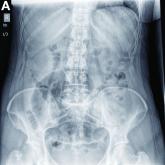

ArticleWhat is your diagnosis? - March 2019Author:Derek J. Erstad, MDPublish date: February 25, 2019Clinical Challenges - March 2019Read More